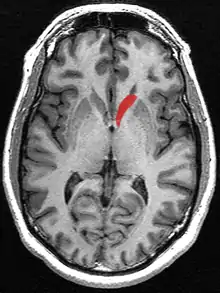

Transverse Cut of Brain (Horizontal Section), basal ganglia is blue | |